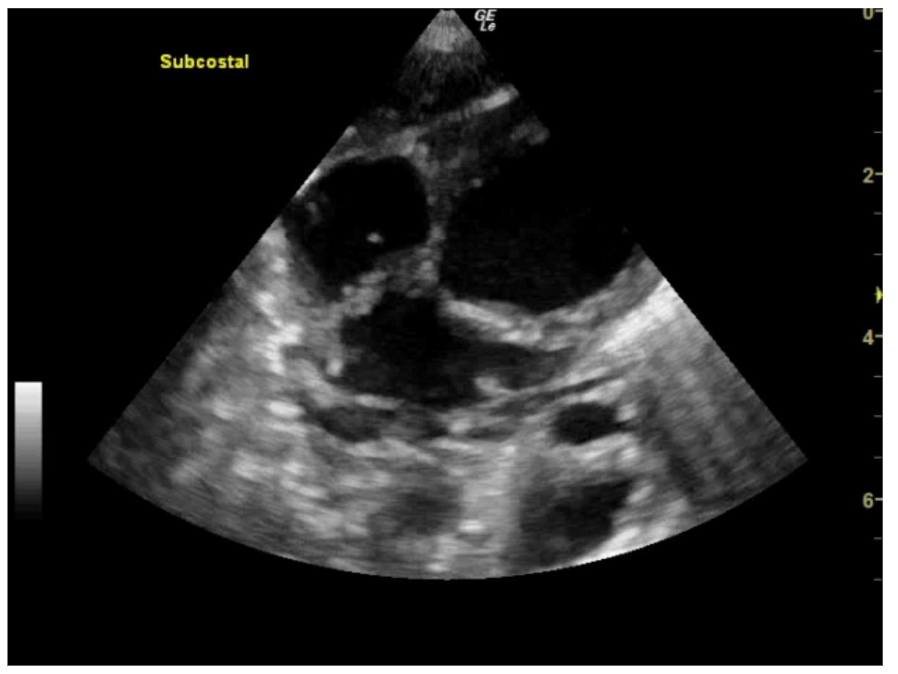

Figure 7: A4C view showing small echogenic masses in the left ventricle, right ventricle and right atrium consistent with septic emboli

Figure 8: SC view showing small echogenic masses in the left ventricle, right ventricle and right atrium consistent with septic emboli. The right atrium is poorly visualised and cannot be assessed https://youtu.be/awqHN68tV2g